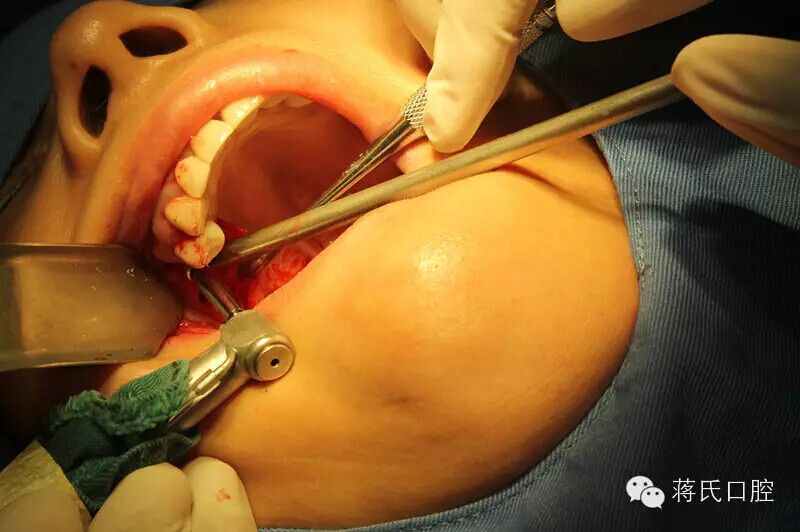

2.右側(cè)種植中

3.備洞過(guò)程中收集自體骨

4.右側(cè)備洞后,以骨擠壓內(nèi)提升方式

5.種植體植入過(guò)程中